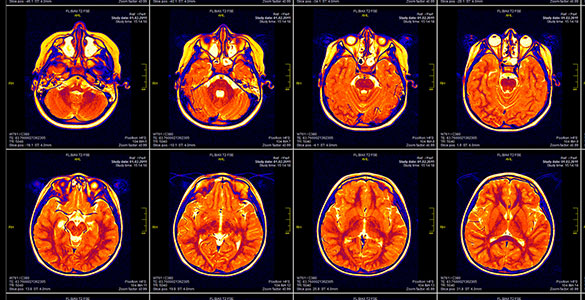

Feed Your Mind: How Food Improves Brain Health Does the food you eat really impact how your brain works? Research says it does! You probably know that eating nutritious meals reduces the risk of many chronic conditions and improves wellbeing. But did you know that a colorful, balanced eating plan also keeps your brain healthy overall? A healthy brain needs enough nutrients to function efficiently over the course of a lifetime. As a Warfighter, the food you choose fuels your body and your mind. Staying focused, having a reliable memory and making sound decisions are all essential functions of a healthy brain and necessary for mission readiness. What Does My Brain Need? Your brain is constantly working. It needs energy to carry out millions of tasks throughout your body to keep you healthy day-to-day. You get energy from food, so what you choose to eat has a direct impact on your brain health. Without enough energy, you likely can’t think as clearly and may have a hard time recalling things compared to when you are properly fueled. Your brain needs enough macronutrients (e.g., carbohydrates, protein and fat) and micronutrients (e.g., vitamins and minerals) to keep you optimally ready. The food you eat affects your brain’s ability to learn, recall and retain information; and adapt to new experiences – all key to strong performance as a Warfighter. Macronutrients CarbohydratesFatsProtein Carbohydrates are your body’s main fuel source. These are broken down into glucose (the simplest form of carbohydrate), which is then used to fuel your brain. Sugars, starches and fibers are all types of carbs. Your brain uses about 20% of your body’s energy needs and it requires carbohydrates for essential functions. It’s recommended to get 45-65% of your daily calories from this macronutrient. Fat is crucial for the brain’s ability to perform. The brain is nearly 60% fat, and some types of fats are better for your brain’s health than others. Omega-3 fatty acids are essential unsaturated fats that play a vital role in brain health. Your body can’t make Omega-3 fatty acids, so you have to get them from the food you eat. It’s recommended to get 20-35% of your daily calories from fat, preferably from unsaturated kinds. Protein provides the building blocks for muscle, bone, cartilage and skin. It’s also essential for producing brain cells and neurotransmitters, the chemical messengers that allow nerves to communicate. There are animal, plant and non-animal sources of protein, all of which contribute to the brain’s energy needs. It’s recommended to get 10-35% of your daily calories from this macronutrient. Micronutrients Fat-soluble Vitamins Fat-soluble vitamins dissolve in fat and are absorbed into your body through dietary fats. They include vitamins A, D, E and K. Fat-soluble vitamins promote vision, bone health, immunity and clotting. Water-soluble Vitamins Water-soluble vitamins dissolve in water and are transported via water throughout your body. They are not stored in the body with the exception of vitamin B12. Water-soluble vitamins include Vitamin C and the B-complex vitamins. They boost immune function, assist with energy production and promote brain and nerve health. Minerals Minerals play a vital role in bone formation, enzyme and hormone function and immune system support. Macrominerals like calcium, magnesium and sodium are needed in larger amounts. Microminerals like iron and zinc are needed in trace, or small, amounts. Building an Eating Plan that Supports Brain Health It’s no surprise foods that support brain health also support your physical health. It’s all connected! When choosing what to eat, aim for nutrient-dense foods over calorie-dense foods. Ultra- and high-processed foods are often calorie-dense and provide less health benefits than nutrient-dense foods. A balanced eating plan includes: Colorful fruits and vegetables, especially dark, leafy greens All 3 macronutrients, especially complex carbohydrates, lean proteins and healthy fats (including foods with Omega-3 fatty acids) Grains, with 50% or more being whole grains Low-fat dairy products like cottage cheese, milk and yogurt Unhealthy Eating Behaviors to Be Mindful Of Just as there are behaviors that support brain health, there are behaviors that can be harmful. Take a moment to reflect on your relationship with food and the habits influencing your food choices. Your brain needs nutrients to function properly. If your brain doesn’t get enough or the right nutrients it needs, you may experience reduced concentration, moodiness (i.e., feeling hangry) and poor decision-making. Over time, not getting enough nutrients may lead to eating disorders, loss of brain tissue and damaged neural connections (e.g., brain function). If you intentionally or unintentionally experience any of the behaviors below, consider speaking to your health care provider about ways to improve your eating habits. Restricting certain ingredients/foods or entire food groups Consuming certain ingredients/foods or food groups in excess Using extreme diets for weight loss or physical outcomes Not meeting your basic caloric needs (e.g., less than 1500 calories per day for men and less than 1200 per day for women) Obsessively thinking about the foods you are consuming Brain health isn’t solely supported by your eating plan. Other health behaviors are also important factors in keeping a sharp mind over time. Prioritizing movement throughout your day, getting 7-9 hours of quality sleep within a 24-hour period and managing your stress also preserve operational strength, endurance and wellbeing. As you evaluate and improve your eating habits, think about how it can amplify your operational readiness. ReferencesAmerican Heart Association - “Food for thought: How diet affects the brain over a lifetime”Arshad, M. T. et al. - “ole of Dietary Carbohydrates in Cognitive Function”Gomez-Panilla, F. - “Brain foods: the effects of nutrient on brain function”Harvard Health - “Foods linked to better brainpower”Mayo Clinic Health System - “Maximize memory function with a nutrient-rich diet”Muth, A-K. & Park, S. Q. - “The impact of dietary macronutrient intake on cognitive function and the brain”National Institutes of Health - “Healthy Eating Linked to Better Brain Health”